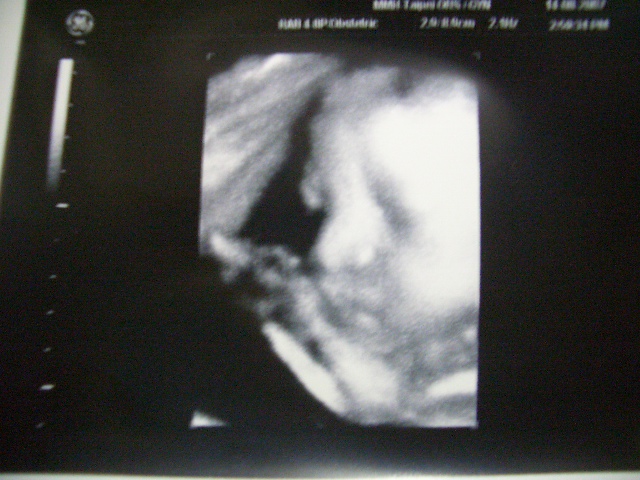

そして、いろんな角度からエコー検査をしていると、赤ちゃんがこっちに顔を向けてくれました!!

すると、先生は気を利かせてくれて『3Dエコー』に切り替えてくれて、写真を撮ってくれました^^

わかりますか??

私とだんな様の赤ちゃんの写真です!!

でも、見るからにだんな様に似ているんですけど・・・

とにかくかわいい私たちの赤ちゃんの顔がこんなにもはっきり見られるなんてとてもうれしく、感動しました。

そして、一番うれしかったのは私のだんな様のようです^^

この写真をずっと見つめてニコニコしていました。

赤ちゃんの顔見た瞬間、出血があったことやもしかしたら筋腫かもしれないことなどすっかり忘れてしまいました。